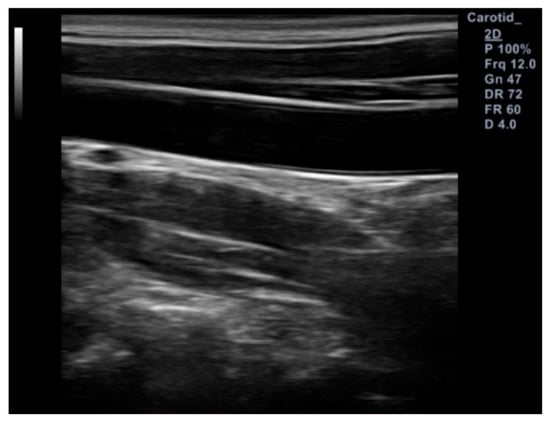

2.2. Experimental Protocols and Data Acquisition